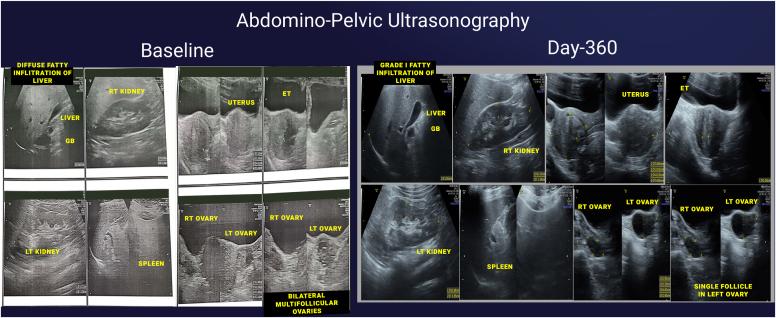

A 38-year-old female with typical PCOS features presented with hypertension, obesity, and elevated fasting and postprandial insulin levels. She was enrolled in the Digital Twin (DT) platform, which uses artificial intelligence and Internet of Things to deliver personalized nutrition by predicting postprandial glucose responses and suggesting alternative foods with lower postprandial glucose response through a mobile app. After 360 days, significant improvements were observed. Weight decreased from 65.4 kg to 57.3 kg (−12.4%); body mass index lowered from 26.2 to 22.96 (−12.4%); Waist circumference reduced from 104 cm to 86.3 cm (−17.0%); clinic systolic blood pressure/diastolic blood pressure reduced from 144/93 to 102/80 mmHg (−29.17%/-13.98%); fasting insulin dropped from 27.6 to 15.5 μIU/mL (−43.8%); postprandial insulin decreased from 182.4 to 23.8 μIU/mL (−87.0%); Homeostatic Model Assessment of Insulin Resistance reduced from 6.47 to 3.48 (−46.2%); estimated glomerular filteration rate improved from 116 to 128 mL/min/1.73m2 (+10.3%); urine microalbumin creatinine ratio decreased from 596 to 73 mg/g (−87.8%). Ultrasound showed reduced ovarian volume and improved fatty liver infiltration, while computed tomography scan revealed significant reductions in epicardial (21.8%), pericardial (69.9%), and visceral fat (44.4%).